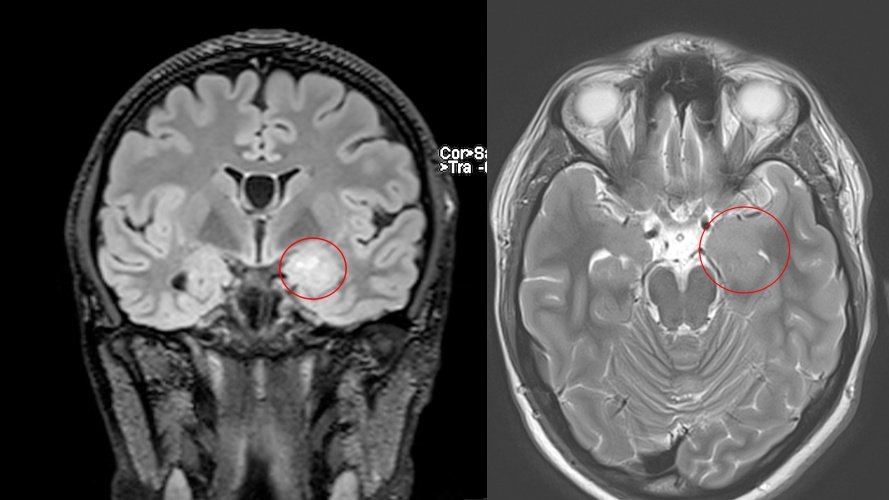

- Descoperită recent, frecvent diagnosticată prin RMN.

- Localizare: De obicei lob temporal.

- Aspect imagistic: Leziuni multinodulare neenhancement, bine delimitate.

- Clinic: Epilepsie.

- Tratament: Observație sau chirurgie dacă simptomatică.

- Grad OMS: 1